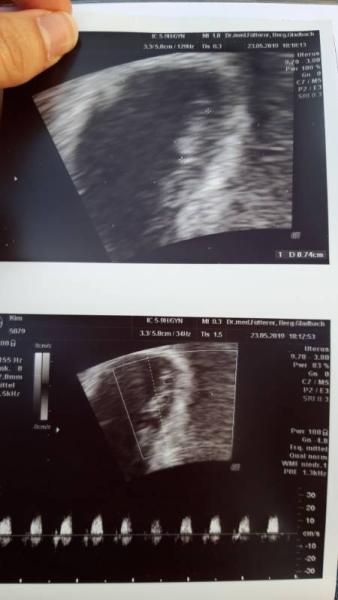

Hey zusammen ich bin in der 8 Woche schwanger und wollt mal hören, ob sich jemand mit der Ramzi Theorie auskennt und mal raten möchte, ob es eher ein junge oder ein Mädchen wird. Ich weiß das man es nie zu 100% sagen kann, wollte nur mal eure Meinung hören. Danke

Ich weis nur das oben das baby ist und unten der dottersack.

Ich glaube weil vaginal geschallt wird ist es spiegelverkehrt aber wie gegesagt ich mich damit auch nicht aus hatte es in einem anderen forum gesehen. Bei mir ist unten der dortersack und oben das baby ubd auf der rechten Seite.

Ahh super dann hab ich es falsch verstanden sorry... Was würdest du dann sagen bei meinem Bild?

Supi dann hab ich das falsch verstanden sorry... Was würdest du dann sagen bei meinen Bild? Mädchen oder?